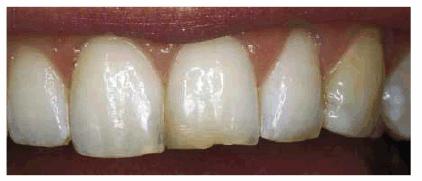

Figur 323s1823d e 18-3A: This young lady fractured her maxillary anterior incisors. Despite numerous bonding repairs, she continued to refracture the teeth. Because she also objected to the incisal translucency, she was treatment planned for three porcelain laminates.

Figur 323s1823d e 18-3B: The initial preparations for the

three porcelain laminates were done with a 0.5-mm depth cutter (Brasseler LVS

System, Brasseler,

Figur 323s1823d e 18-3C: The two-grit diamond is used to reduce the enamel to the predetermined depth cut.

Figur 323s1823d e 18-3D: The final preparations.

Figur 323s1823d e 18-3E and F: Three porcelain laminates were placed on the central incisors and right lateral. The new laminates also achieved the objective to eliminate the incisal translucency.